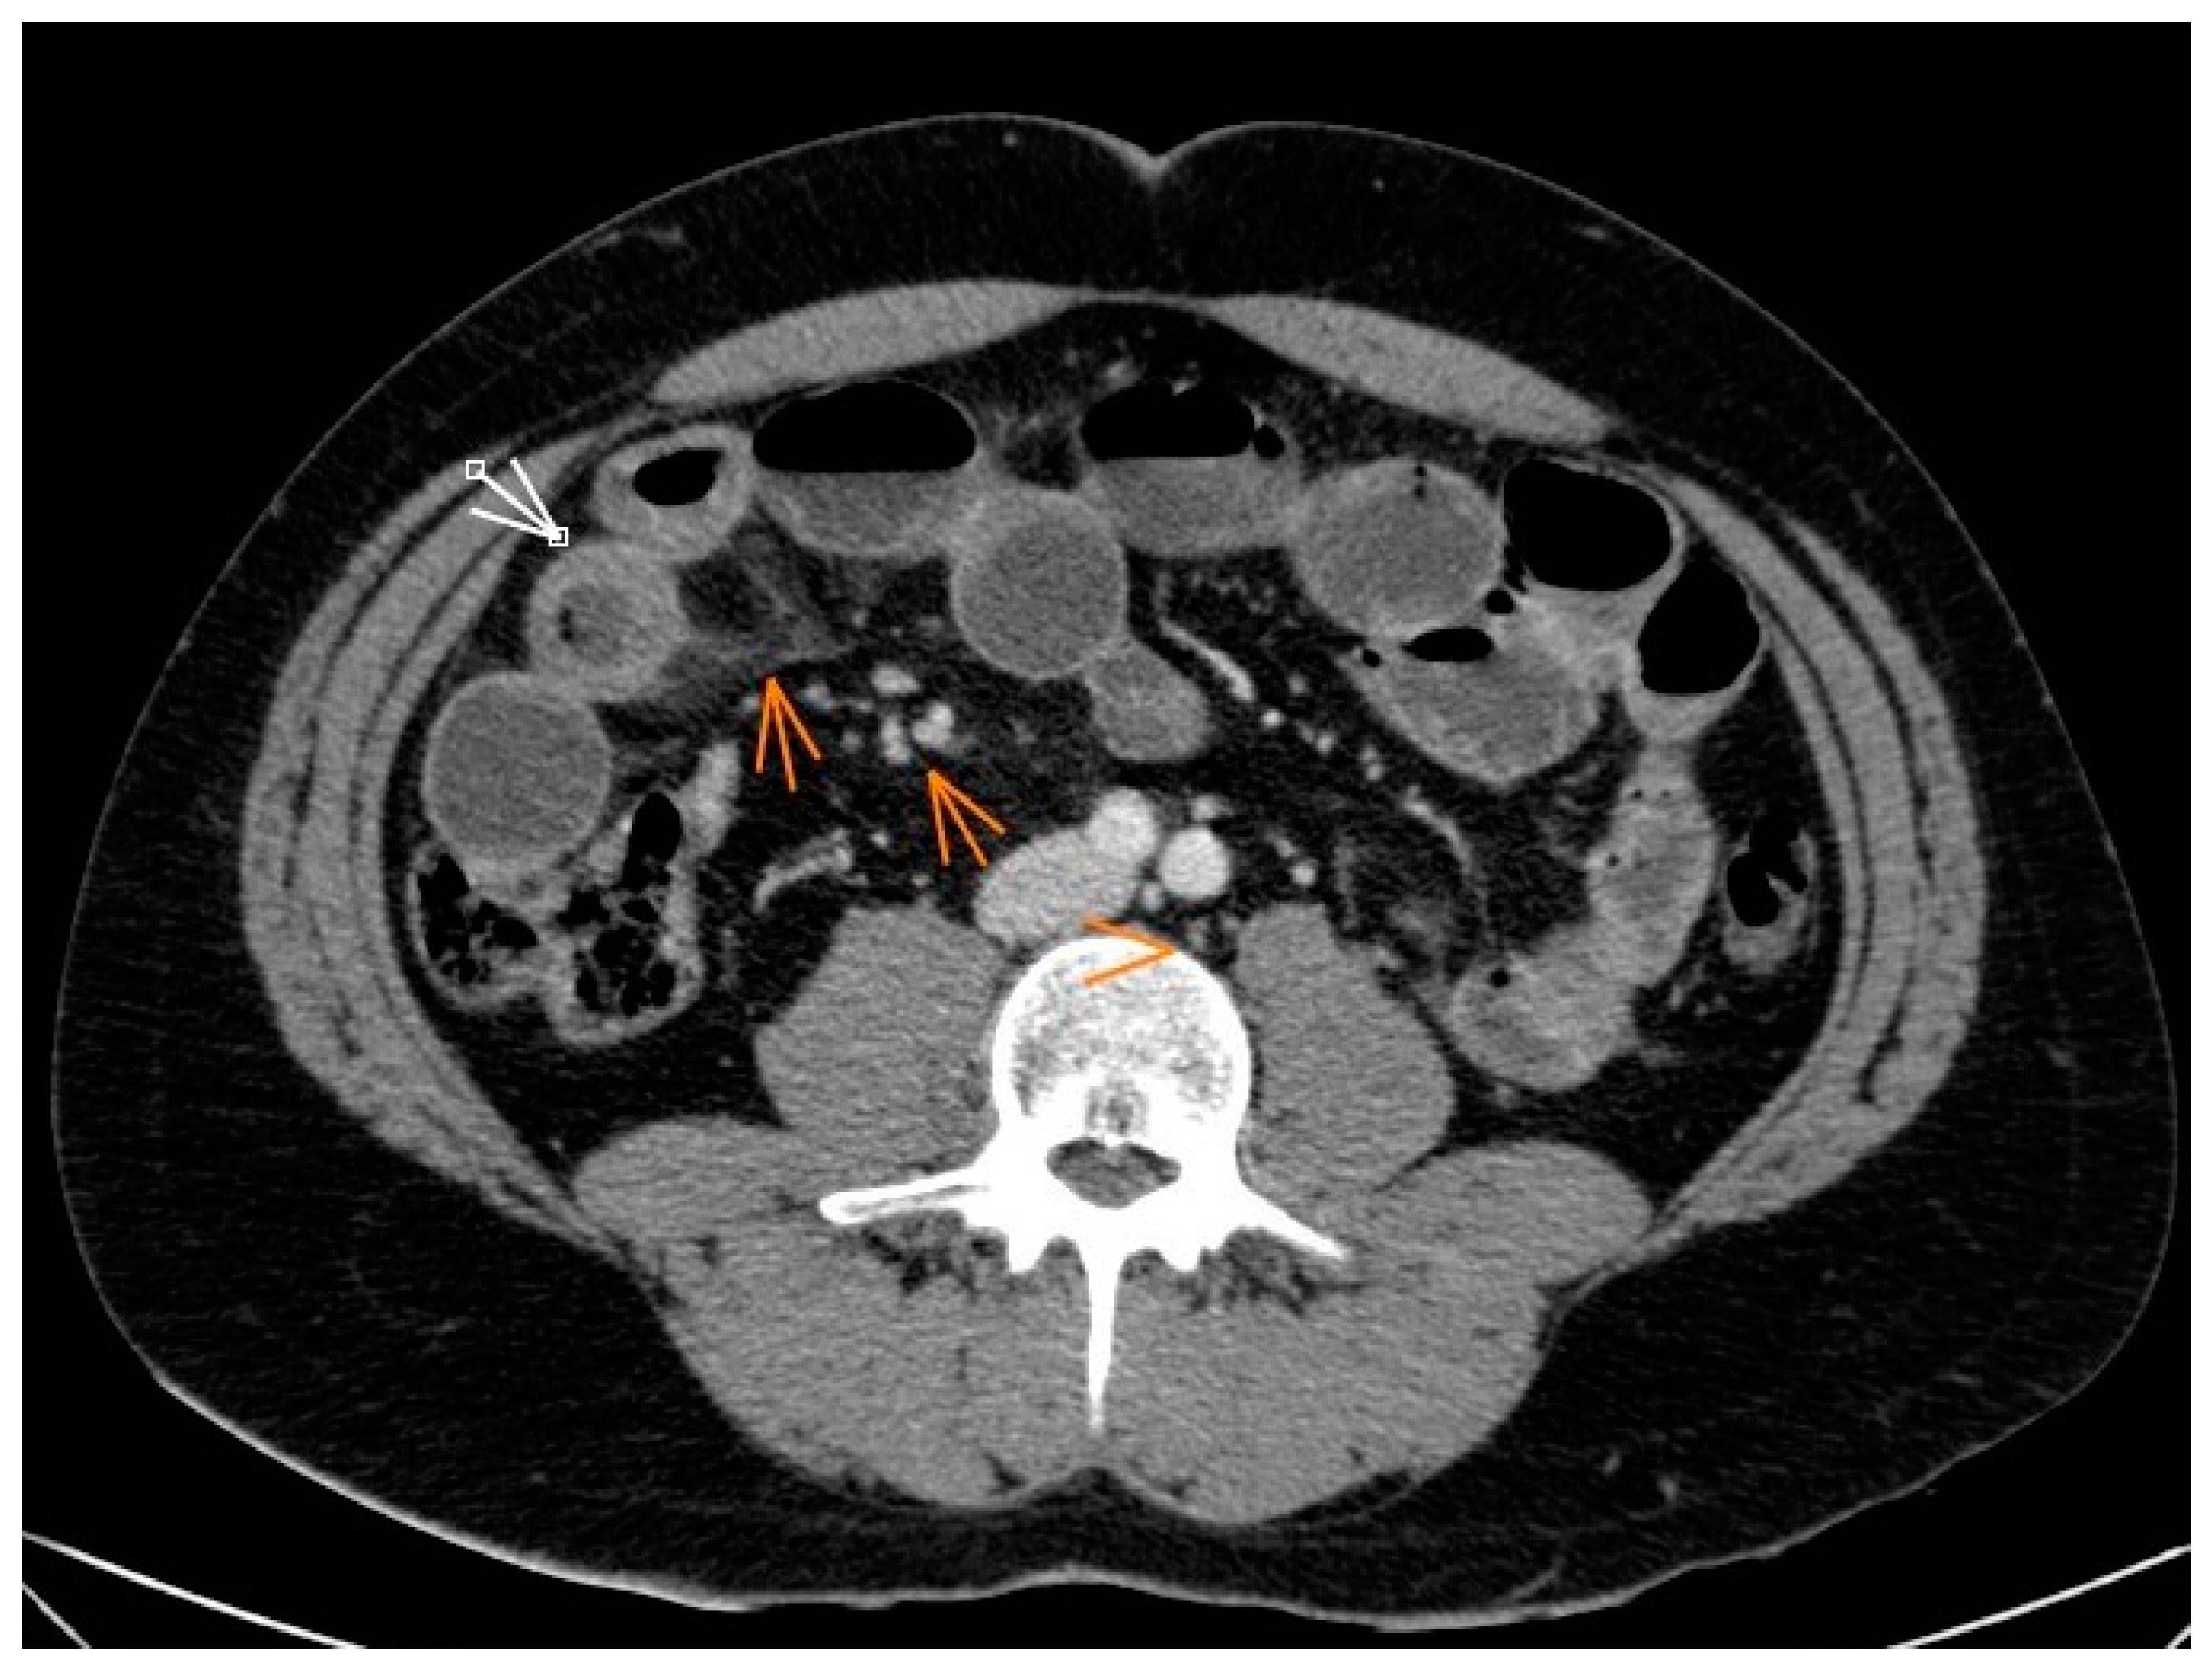

2. Case Description

- Shibata, E.; Ueda, T.; Akaike, G.; Saida, Y. CT Findings of Gastric and Intestinal Anisakiasis. Abdom. Imaging 2014, 39, 257–261. [Google Scholar] [CrossRef]

- Fornell Pérez, R.; Urizar Gorosarri, M.; Pérez Bea, M. Anisakiasis: Imaging findings. Radiologia 2022, 64, 245–255. [Google Scholar] [CrossRef] [PubMed]